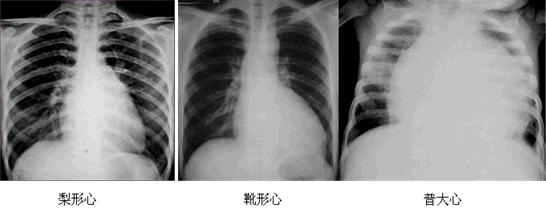

| 二尖瓣型 | 梨形心 | 左心房增大 | 二尖瓣狹窄(最常見(jiàn)) |

| 主動(dòng)脈型 | 靴形心 | 左心室擴(kuò)大 | 法洛四聯(lián)征、主動(dòng)脈瓣膜疾病、高血壓心臟病等 |

| 普大型 | 普大心 | 心界向兩側(cè)擴(kuò)大 | 心肌病、心臟病后期、心包積液等 |